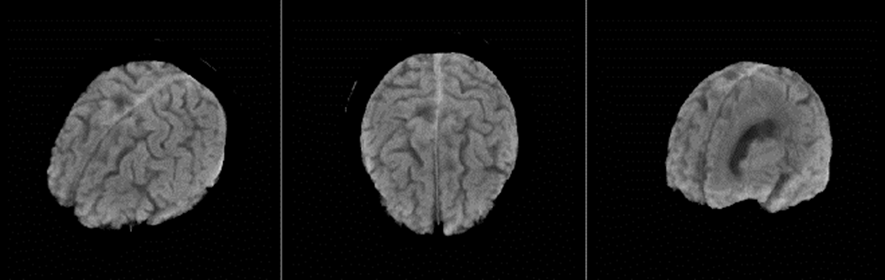

ワンクリック3Dの操作性

選定時に大きなポイントとなった、患者様に分かり易い診断結果を提供したいと言う院長の思いを形にするため、3次元画像解析機能は最も注目した性能の一つでした。 実際に使用してみて、その速さと快適さを実感することができ、従来、複数の手順を踏まなければならなかった脳の 3D画像を、本当にワンクリックで作成でき、患者様への説明に一役買っています。

しかも実際に患者様から「これは分かり易いですね!」との感想も伺うことができ、患者様のニーズにヒットしていると実感しています。

従来のチルトコンベンショナルスキャンによる頭部検査では、脳底部、特に脳幹、小脳付近の画質はあまり良いとは言えませんでした。それがRevolution ACTでは、1.25mmスライスでのヘリカルスキャンができるので、薄いスライスでの収集による効果でアーチファクトが軽減され、また連続したデータであることからMPR(サジタル面、コロナル面)での画質が格段に向上しました。その結果、小脳、脳幹部の診断への信頼度が上がり、また、海馬領もコロナル面での観察が容易にでき、臨床有用性を高めています。